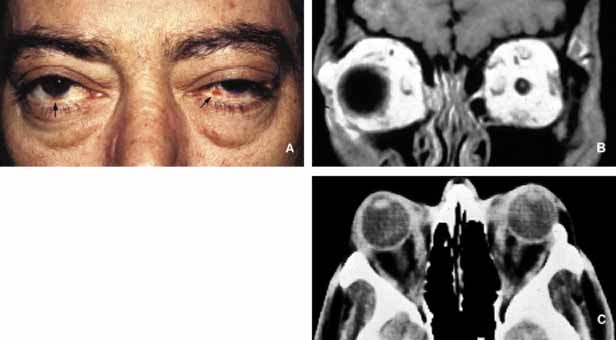

Graves Disease

Thyroid-associated orbitopathy, better known as Graves disease (Gd), is an idiopathic orbital inflammation that primarily involves the muscles and soft tissues of the orbit and the eyelids. The commonly involved muscles include inferior, medial, superior and lateral recti that cause swelling of the tissue leading to proptosis and eyelid retraction (Fig. 9). Gd is the most common cause of unilateral and bilateral proptosis in adults; although uncommonly it may be seen in children as well.

Fig. 9 Graves disease. Clinical findings of Graves disease are depicted in frame A, including bilateral proptosis and lid lag with extraocular motility disturbance, chemosis with prolapse of lacrimal gland and congestion of conjunctival and episcleral blood vessels. Axial CT scan (B) reveals marked swelling of all recti muscles. The histopathologic appearance of the extraocular muscle from a patient with Graves disease reveals chronic inflammatory infiltrates, primarily composed of lymphocytes and plasma cells (C). The extraocular muscle volume is increased because of diffuse endomysial fibrosis, mucopolysacccharide deposition and chronic inflammatory cell infiltration (D). The orbital fat, meninges and the optic nerve (blue arrow), large blood vessels of the orbit, such as ophthalmic artery and its branches (green arrows) and the ciliary ganglion (red arrow) do not show any inflammation. The enlargement of the extraocular muscles are well depicted in frame E, which represents a transverse section, approximately at the level indicated by the yellow line in frame B. (LR: lateral rectus; SR + L: superior rectus and levator complex; SO: superior oblique; MR: medial rectus; IR: inferior rectus; IO: inferior oblique). (Frames C, D, and E are the courtesy of Ralph C. Eagle, MD of Philadelphia, PA)

Although 80% of patients with Gd present with a history of hyperthyroidism, approximately 10% suffer hypothyroidism or autoimmune thyroiditis; occasionally, an euthyhroid individual may also develop the signs and symptoms of Gd.102 Upper lid retraction is the most frequent clinical sign in early Gd (75%) followed by asymmetrical bilateral proptosis (60%) and restriction of extraocular muscles (40%). Compressive optic neuropathy may result secondary to the enlargement of the extraocular muscles in the apex. Optic nerve malfunction is manifested by afferent pupillary defects and color vision and visual field deficiencies in approximately 5% of Gd patients.

The best means of evaluation of extraocular muscles is imaging with CT and/or MRI.11 Axial CT scan is very valuable to depict the enlargement of the extraocular muscles and determine whether there is any infiltration into other orbital soft tissues. Coronal sections are also very useful to evaluate the enlargement of the muscles and their relationship to the optic nerve in the orbital apex.103 In differential diagnosis of Gd, one should keep in mind that it is not only the most frequent cause of bilateral proptosis but unilateral proptosis as well. Therefore, the slowly progressive unilateral presentation may be confused with orbital pseudotumors, neoplasia, and solitary vascular lesions such as orbital varix.104,105 Orbital metastatic neoplasms may also be confusing if they are limited to the extraocular muscles. Imaging usually reveals nodular enlargement of the muscle and the diagnosis of a metastatic disease may be confirmed with fine needle aspiration biopsy (FNAB). The treatment of Gd includes oral and intravenous steroids, radiation and surgery.